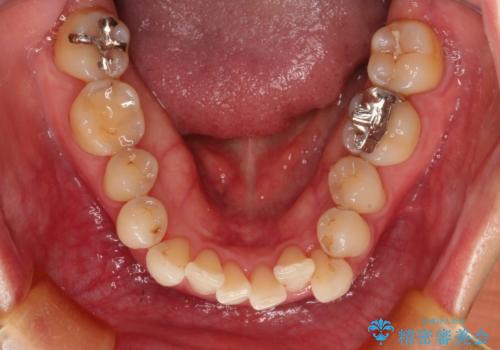

八重歯のインビザライン矯正治療

- 下顎の八重歯と、上下のクロスバイトを気にして来院された患者様です。

インビザラインを用い、下顎全体の後方移動、IPR(歯と歯の間を削る)と歯列全体を拡大させることで、歯並びを整えていくこととしました。

奥に位置していた上の前歯が下の前歯を乗り越える際、奥歯でものを咬むことができず、辛い時期が続きました。